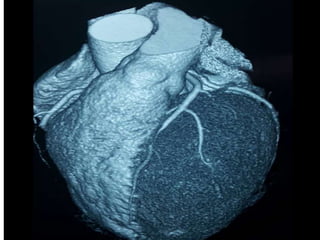

CASO CLINICO # 3

MASCULINO 65 AÑOS DE EDAD

DIABETES TIPO 2 DESDE HACE 15 AÑOS POBRE CONTROL METABOLICO

DISLIPIDEMIA. OBESIDAD GRADO II.

CUADRO CLINICO: ANGINA DE PECHO ATIPICA. CHEQUEO DE RUTINA. ECG DE

REPOSO NORMAL. PRUEBA DE ESFUERZO POSITIVA Y PRECOZ PARA ISQUEMIA.

TA 120/ 68 mm Hg. FC 67/min Fr 13/ min

Glucosa en Ayunas 215 mg /dL. Colesterol total 260 mg/dL, LDL 135 mg d/L

Creatinina 1.2 mg/dL

EXAMEN FISICO ANODINO

CASO CLINICO #3 MASCULINO 65 AÑOS DE EDAD DIABETES TIPO 2 DESDE HACE 15 AÑOS POBRE CONTROL METABOLICO DISLIPIDEMIA. OBESIDAD GRADO II. CUADRO CLINICO: ANGINA DE PECHO ATIPICA. CHEQUEO DE RUTINA. ECG DE REPOSO NORMAL. PRUEBA DE ESFUERZO POSITIVA Y PRECOZ PARA ISQUEMIA. TA 120/ 68 mm Hg. FC 67/min Fr 13/ min Glucosa en Ayunas 215 mg /dL. Colesterol total 260 mg/dL, LDL 135 mg d/L Creatinina 1.2 mg/dL EXAMEN FISICO ANODINO